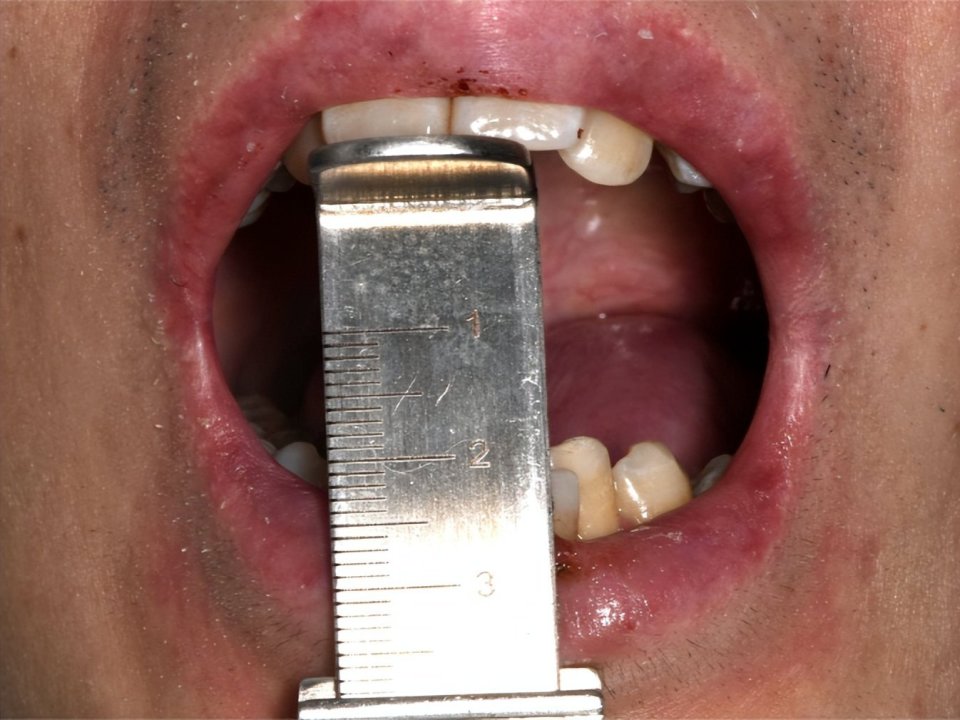

3、张口受限与味觉障碍

黏膜下组织的进行性纤维化(硬化),可导致组织弹性丧失,引发渐进性张口受限,不仅限制饮食选择,更使得日常口腔卫生维护和必要的牙科治疗变得极其困难5。同时,舌乳头萎缩导致的味觉减退或异常,与口腔敏感、疼痛叠加,使“吃饭”变为折磨,严重影响食欲与情绪。

口周硬化与张口受限表现(图片源自陶人川教授团队)